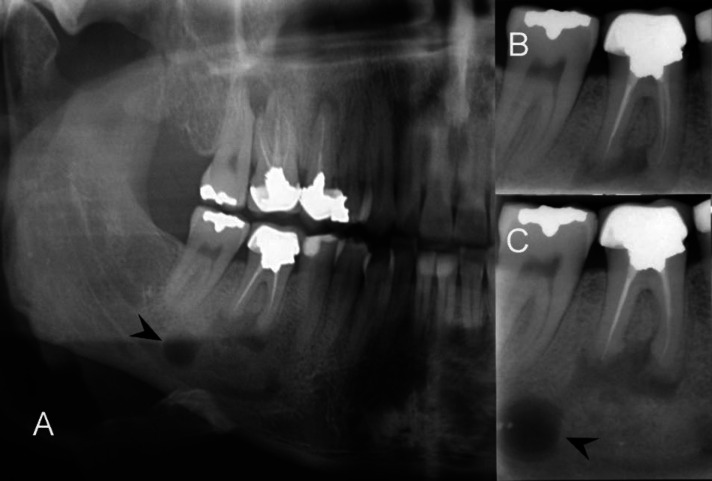

本病例报告旨在记录一名 35 岁男性患者的罕见远端牙源性病变,该患者下颌右侧第一磨牙有轻微的临床不适;探讨了不常见的远端牙髓病变的诊断和治疗的复杂性,最终通过细致的非手术再治疗得到了解决。尽管口腔检查结果正常,但放射诊断检查却显示根管治疗效果不佳,根尖中、远端病变环绕根尖;包括通过全景放射检查发现的下颌第二磨牙根尖下方的明显放射线,并经锥形束计算机断层扫描证实。此外,计算机断层扫描还发现了一个以前从未报道过的、异常巨大的牙髓病变,该病变向下颌管延伸;这凸显了继续探索这一独特牙髓病变的必要性。非手术的牙髓再治疗使放射状病变在一年内显著缩小;强调了综合诊断方法和个体化治疗的重要性。

The current case report aims to document a rare presentation of a distant odontogenic lesion of a 35-year-old male patient with mild clinical discomfort in the mandibular right first molar; exploring the diagnostic and therapeutic intricacies of an uncommon distant endodontic pathosis ultimately resolved through meticulous nonsurgical retreatment. Despite a normal oral examination, diagnostic radiography revealed a suboptimal root canal treatment and apical lesions surrounding mesial- and distal-root apices; including a distinct radiolucency beneath the apex of the second mandibular molar discovered through panoramic radiography, and confirmed via cone-beam computed tomography. In addition, the computed tomography disclosed a previously unreported and unusually large endodontic lesion that extended toward the mandibular canal; highlighting a necessity for the continued exploration of a unique endodontic presentation. A nonsurgical endodontic retreatment led to a remarkable reduction in the radiolucent lesions within one year; emphasizing the significance of comprehensive diagnostic approaches and individualized treatments.